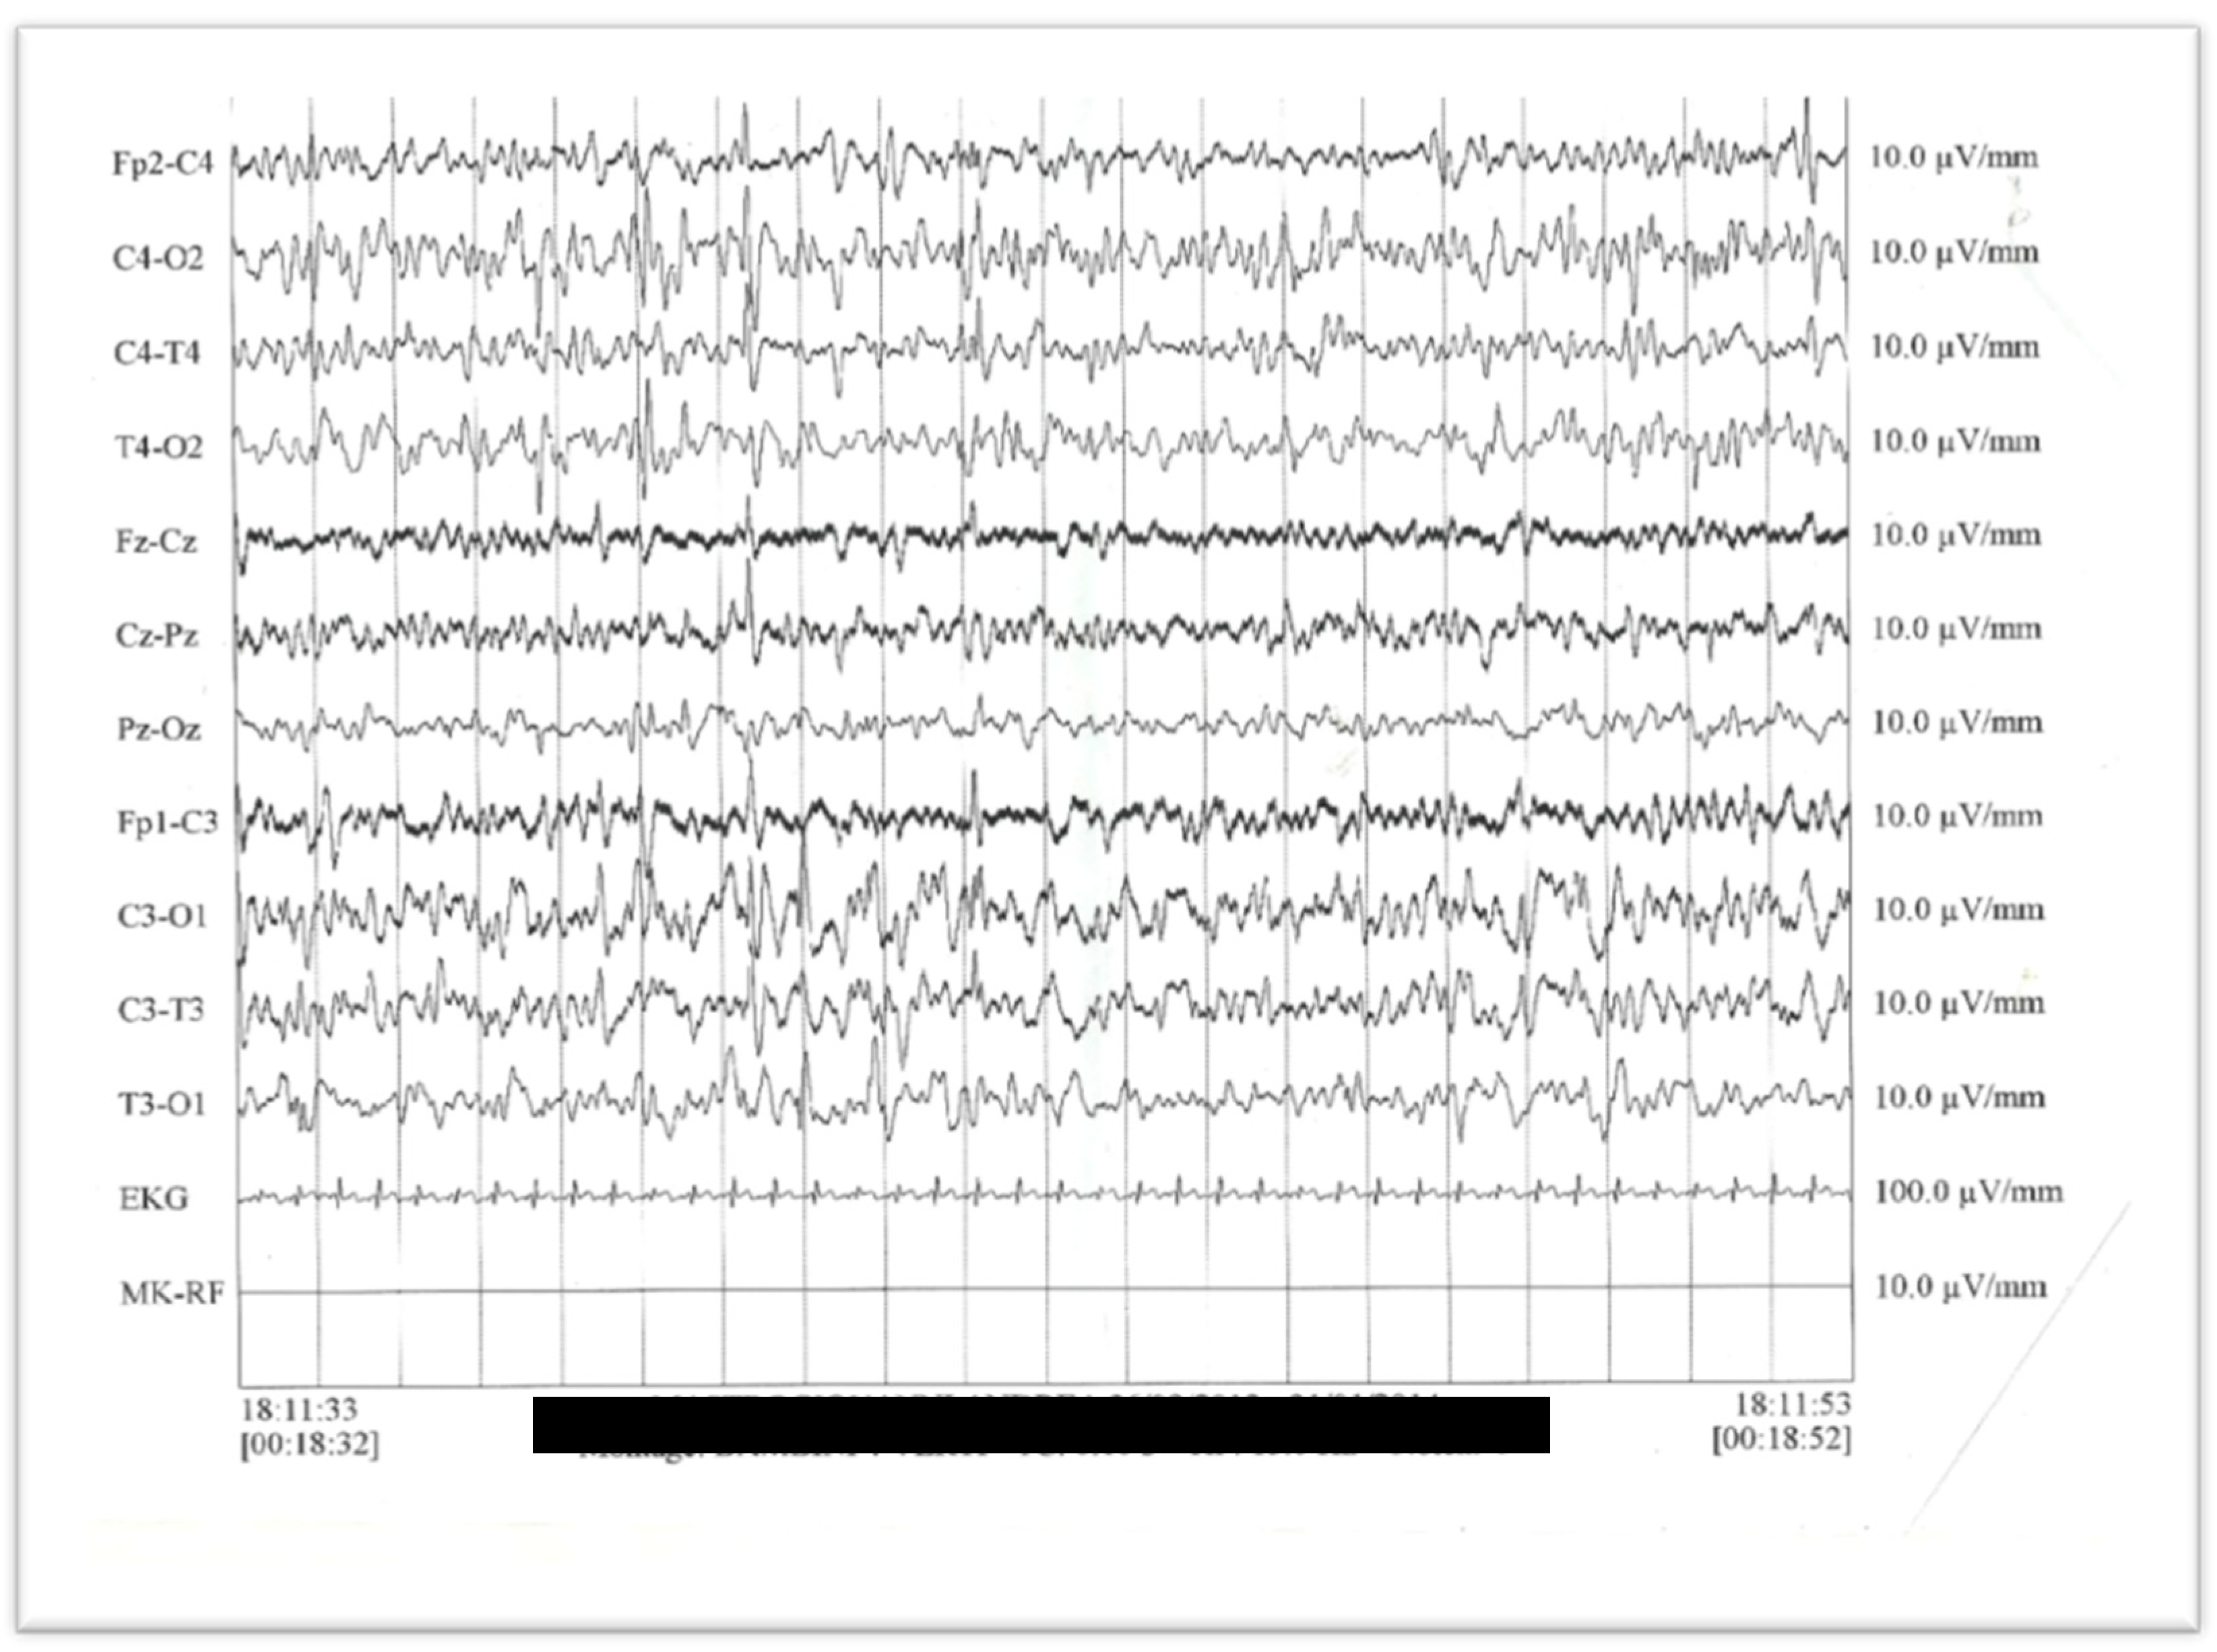

3.1. Case Report